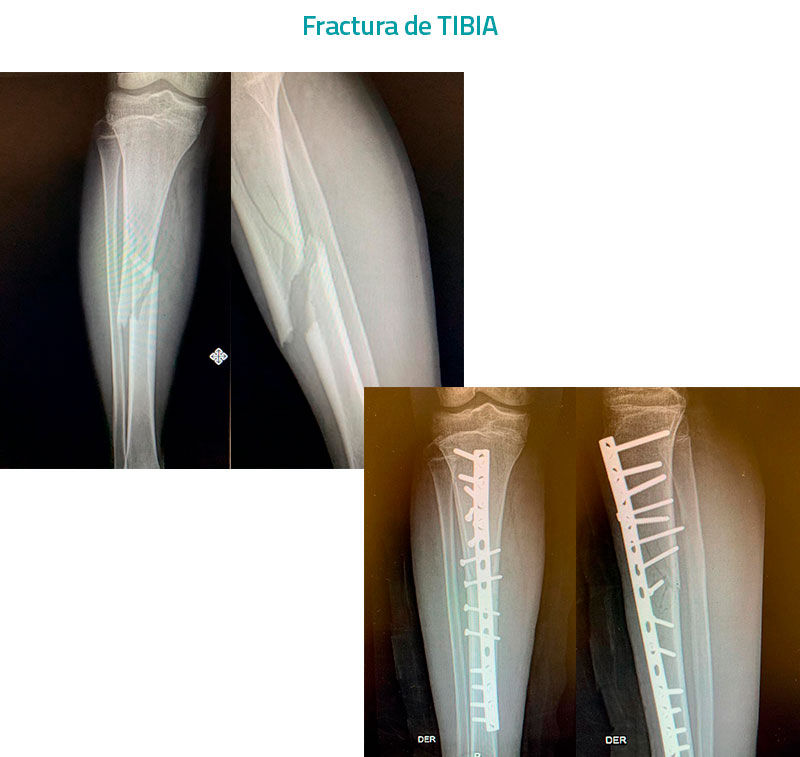

Fractura-de-TIBIA

Cirugía por Fractura

Una fractura es la solución de continuidad de un hueso, en su mayoría secundaria a un traumatismo que puede ser de alta o baja energía, ya que existe otro tipo de fracturas en las que no este implicado un mecanismo traumático, el manejo de una fractura dependerá de si es una fractura abierta, también conocida como expuesta o cerrada, ya que las primeras son urgencias y siempre requerirán de un manejo quirúrgico de manera prioritaria, consistente en el aseo quirúrgico del sitio afectado con diversas soluciones, la debridación del sitio y de algún manejo de osteosíntesis que se podrá realizar en un mismo tiempo siempre y cuando el tiempo de evolución sea menor a 6 horas y el grado de exposición sea menor y no implique la contaminación del sitio de fractura, ya que de lo contrario previo a la osteosíntesis definitiva se deberá impregnar con antibiótico por algunos días con protocolos ya establecidos en base al grado, así mismo cuando eso sucede se puede estabilizar temporalmente con un fijador externo hasta que sea posible realizar la osteosíntesis definitiva la cual podrá llevarse a cabo con los diferentes implantes con los que se cuenta y que serán determinados por la personalidad de la fractura, en tanto una fractura cerrada puede ser susceptible de un manejo conservador a base de una reducción cerrada y estabilización con un molde de yeso, de fibra de vidrio o de alguna férula de los mismos materiales o incluso de una ortesis, así como otras requerirán de un manejo quirúrgico el cual puede llevarse a cabo con los diferentes implantes con los que se cuenta y que dependerán de la personalidad de la fractura, pero también de la edad del paciente, de las condiciones del hueso, de enfermedades concomitantes, entre otras situaciones, que pudieran de requerir del uso de un implante especial.